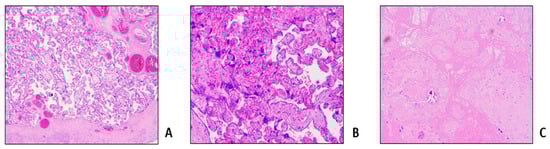

- Malinowski, A.K.; Dziegielewski, C.; Keating, S.; Parks, T.; Kingdom, J.; Shehata, N.; Rizov, E.; D’Souza, R. Placental histopathology in sickle cell disease: A descriptive and hypothesis-generating study. Placenta 2020, 95, 9–17. [Google Scholar] [CrossRef] [PubMed]